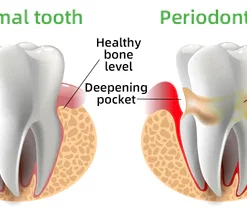

Every day, food residues in our mouths create a breeding ground for various bacteria and microorganisms within the oral cavity. This can result in a range of oral health issues, including bad breath, mouth ulcers, yellow teeth, cavities, calculus buildup, gum inflammation, bleeding gums, tooth sensitivity, weakened or missing teeth, swollen gums, toothaches, loose teeth, tooth loss, and even the risk of oral cancer.

As these conditions worsen, you may experience persistent bad breath, gum inflammation, and other problems. Bacteria continue to harm your gums, leading to issues like bleeding, pain, and redness. Without timely intervention, these oral problems can escalate, potentially causing periodontitis, dental plaque, dental calculus, loose teeth, tooth pain, and eventually tooth loss.

Dental caries develop when germs damage tooth enamel and gradually penetrate into the dentin and even the pulp. This can result in bad breath, toothaches, weakened teeth, and potential tooth loss. The presence of caries often triggers a chain reaction, causing healthy teeth to be affected as germs spread to adjacent teeth.

Remove Calculus

Calculus is calcified dental plaque that inflames the gums, which can lead to bone loss, loose teeth, tooth sensitivity, etc. FURZERO™ Herbal Brightening Oral Repair Foam can help eliminate dental plaque and remove stubborn calculus attached to teeth, making your teeth white and healthy again.